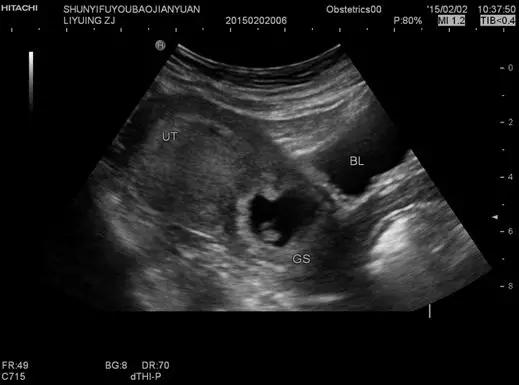

经腹壁扫查最常见(即腹式B超),是将B超探头放在下腹部观察盆腔内,重点检查子宫、卵巢及附件区的情况。在检查前半小时至1小时需要饮水1000ml左右,并且要憋尿憋到最大的限度。因为只有膀胱充盈到一定程度,才能将子宫从盆腔深处挤到下腹部,通过图像的明暗对照,清楚的观察到子宫及卵巢,所以最好随身携带水瓶及时补充。憋尿后接受检查时会有一点儿胀痛。

阴超频率比腹部常规用探头高,分辨率比腹部探头明显增强。探头在阴道内紧贴宫颈及后穹窿,不像腹部B超,声束要经过腹壁皮肤、肌肉、膀胱、肠道,所以盆器显示更清晰。尤其是对后位子宫、子宫内膜癌、子宫肌瘤、后盆腔肿块、卵泡监测、早期宫外孕(未破前)、早早孕、前置胎盘等观察,图象显示比经腹部B超明显清晰。对早早孕的检测,比腹式B超早发现5-7日。不需憋尿,为患者争取时间,且患者不受充盈膀胱之不适。